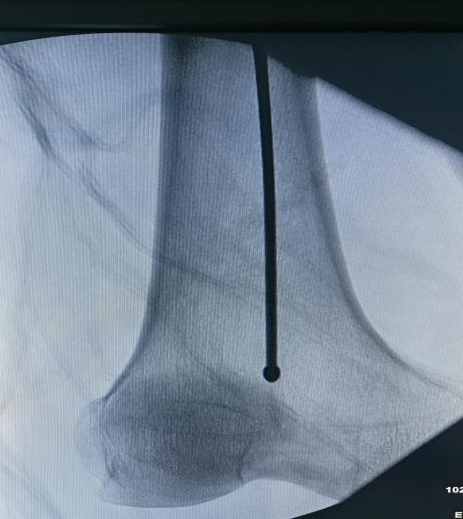

InterTAN versus proximal femoral nail anti-rotation for intertrochanteric fractures in the elderly: a comparison of joint function and stability

He Yun, Yiliyaer · Abudusimu, Xu Bin, Wang Guosheng

2026, 30 (21):  5460-5467.  doi: 10.12307/2026.622

Abstract ( 10 )   PDF (2996KB) ( 7 )   Save

BACKGROUND: Elderly patients with intertrochanteric fractures often have multiple medical comorbidities and significant osteoporosis, posing considerable challenges for treatment. Proximal femoral nail anti-rotation and InterTAN are both commonly used intramedullary fixation systems. However, there remains insufficient evidence regarding the optimal selection of fixation systems for patients with different medical conditions and fracture types.

OBJECTIVE: To compare the clinical outcomes and complication differences between integrated compression screw and lag screw intertrochanteric nail (InterTAN) and proximal femoral nail anti-rotation in the treatment of elderly patients with intertrochanteric fractures.

METHODS: A prospective randomized controlled trial was conducted. A total of 118 elderly patients with intertrochanteric fractures who met the inclusion criteria were enrolled. Patients were randomly divided into groups. The proximal femoral nail anti-rotation group (59 cases) underwent internal fixation with proximal femoral nail anti-rotation, and the InterTAN group (59 cases) underwent internal fixation with InterTAN. Perioperative parameters, including operation time, intraoperative blood loss, fluoroscopy frequency, and hospital stay, were recorded. Follow-up assessments were conducted at 1, 3, 6, and 12 months postoperatively. The fracture healing rate, internal fixation stability, and complications were evaluated using Harris hip scores and imaging examinations.

RESULTS AND CONCLUSION: (1) Operation time, intraoperative blood loss, and fluoroscopy frequency in the proximal femoral nail anti-rotation group were significantly lower than those in the InterTAN group (P < 0.001). No significant difference was found in hospital stay (P > 0.05). (2) The fracture healing rates were similar between the two groups at 12-month follow-up (P > 0.05). At 12 months, the incidence of instability was significantly lower in the InterTAN group (P < 0.05). Harris scores in terms of pain, function, and joint mobility in the InterTAN group were significantly superior to those in the proximal femoral nail anti-rotation group (P < 0.05). There was no significant difference in overall complication rates between the two groups (P > 0.05). (3) These results indicate that proximal femoral nail anti-rotation has certain advantages in reducing perioperative trauma, whereas InterTAN demonstrates greater potential value in terms of fixation stability and functional recovery at the 1-year follow-up. Clinical selection of internal fixation systems should be based comprehensively on the patient's condition and fracture type.